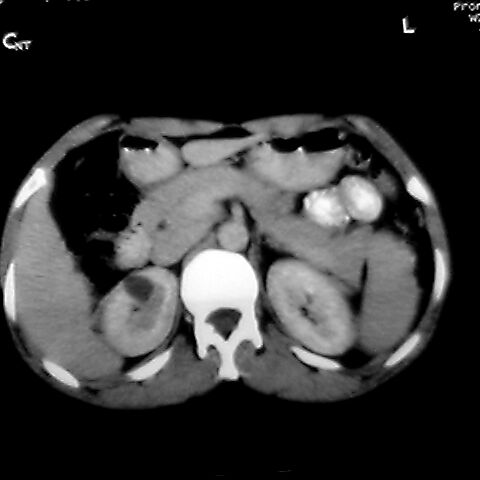

女 48岁 食道癌术前体检发现脾占位。

右肾见类圆形低密度影.结合病史.脾及右肾转移性ca可能性大

转移瘤不可能单发,考虑脾血管瘤。

1,脾血管瘤。2,右肝,右肾小囊肿。